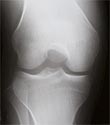

X-ray of Knee Without Arthrits

X-ray of normal knee and knee with arthritis. Notice the loss of joint space with bone touching bone in the knee with arthritis.

X-ray of Knee With Arthritis